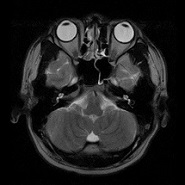

MRIは磁気共鳴画像とも呼ばれ、強い磁石と電波を使って、身体のあらゆる部位を撮影できる装置です。放射線を使用しないので被ばくの心配はなく、ラジオ波と同じ電波を利用して撮影しているため人体に優しい検査法です。 X線の画像と比べて筋肉・脊髄・内臓などが、明瞭かつ詳細に描出されます。MRIが有用なのは、脳梗塞・脳腫瘍などの脳疾患、動脈瘤などの血管障害、がん・子宮筋腫・椎間板ヘルニア・靭帯断裂など動きの小さい柔らかい組織での病変描出に適しています。 MRIの特性を利用して、造影剤を使わずに脳血管像(MRA) 胆管・膵管像(MRCP)の描出も可能です 。

実際の検査画像

| 頭部 | 頸椎 | 腰椎 | 腹部 |